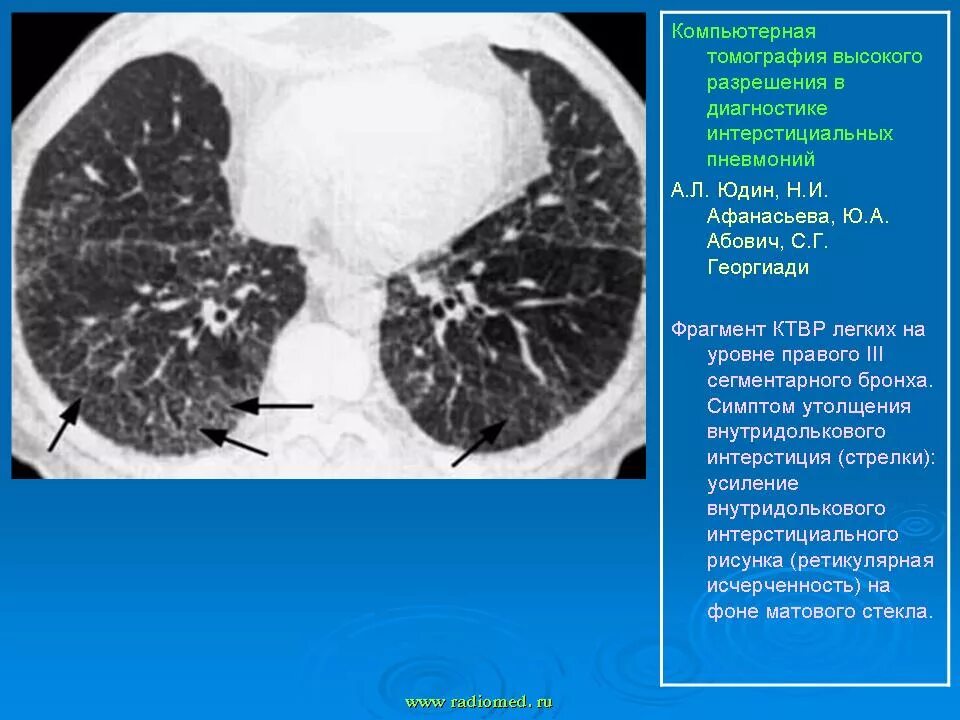

Ретикулярные изменения это